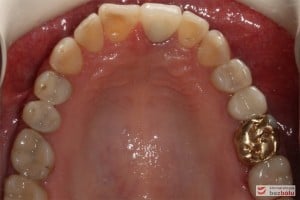

Do naszej placówki zgłosiła się starannie planująca swoje działania Europejka, mieszkająca na stałe w Kotlinie Jeleniogórskiej. Jej oczekiwania dotyczyły bardzo metodycznie zaplanowanego planu leczenia. Celem jaki postawiła przed naszym zespołem lekarzy było wyeliminowanie wszystkich wątpliwych i nierokujących wypełnień, a także poprawa estetyki w zakresie lewego siekacza centralnego w szczęce. Został rozpisany blisko dwuletni plan wymiany zużytych i nieszczelnych wypełnień amalgamatowych i kompozytowych. Zaplanowano również przygotowanie endodontyczne wybranych zębów w szczęce i żuchwie, a także zaopatrzenie w inlay’e porcelanowe i korony ceramiczne wykonane w systemie e-max.